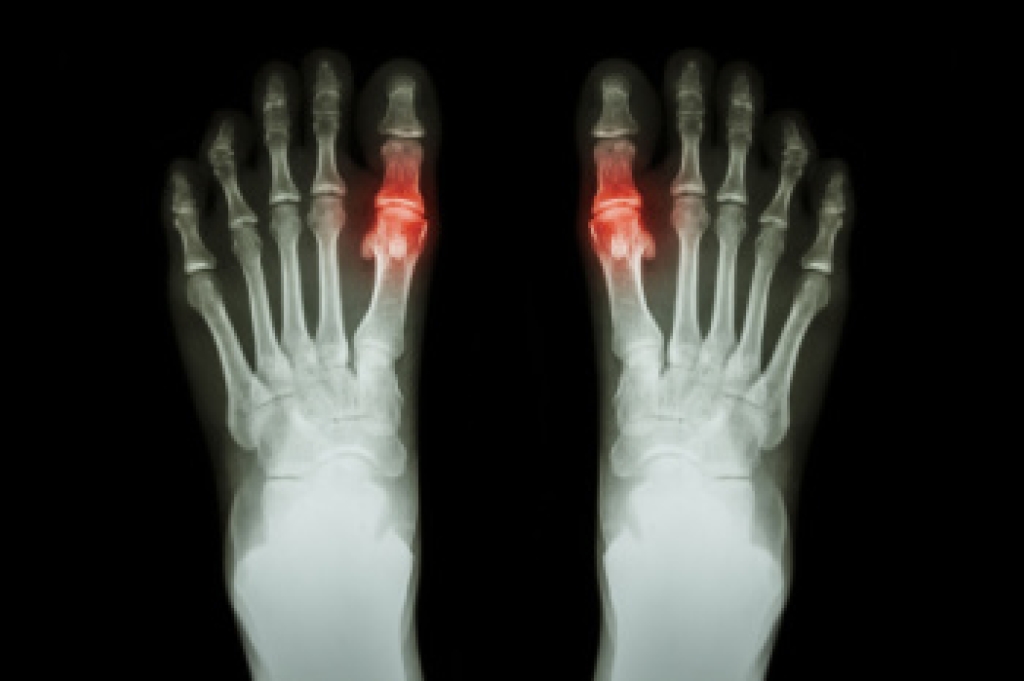

Gout is a form of arthritis that causes sudden and severe pain, often affecting the joints, particularly the big toe joint. The condition occurs when excess uric acid builds up in the body, forming crystals in the joints. The most common sign of gout is intense pain, typically starting in the middle of the night, along with swelling and redness in the affected area. The joint may become warm to the touch and feel tender, making movement difficult. In some cases, gout attacks can recur, leading to joint damage over time. Elevated uric acid levels in the blood can result from factors such as diet, dehydration, obesity, or kidney problems. Excessive consumption of purine-rich foods like red meat, seafood, or alcohol can trigger or worsen gout attacks. If you have had one or more gout attacks, it is suggested that you are under the care of a podiatrist who can offer you effective relief and management tips.

Gout is a painful condition that can be treated. If you are seeking treatment, contact one of our podiatrists from Lewis Wolstein, DPM, P.C. & Associates. Our doctors will treat your foot and ankle needs.

What Is Gout?

Gout is a form of arthritis that is characterized by sudden, severe attacks of pain, redness, and tenderness in the joints. The condition usually affects the joint at the base of the big toe. A gout attack can occur at any random time, such as the middle of the night while you are asleep.